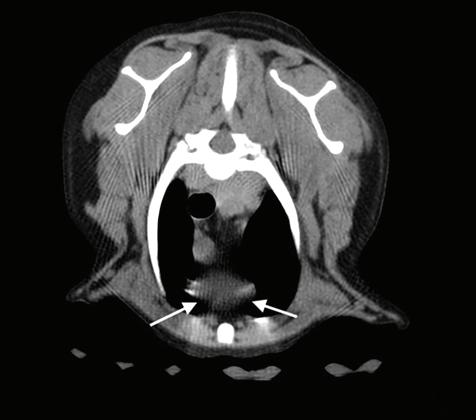

Figura 1. Radiografías torácicas en proyección lateral derecha (A) y ventrodorsal (B) donde se visualiza el área de opacidad de tejido blando craneal a la silueta cardíaca (flechas blancas). En la proyección ventrodorsal se visualiza el mediastino craneal que se presenta en el límite superior de grosor (flechas rojas).

A B A B

Se realizaron radiografías torácicas y en la proyección lateral derecha se observó, craneal a la silueta cardiaca, una opacidad tejido blando mal definida que producía efecto silueta positivo con esta. La tráquea se visualizó desplazada dorsalmente y el atrio izquierdo aumentado de tamaño. El parénquima pulmonar mostraba un aumento de opacidad en su área caudodorsal, compatible con un patrón pulmonar intersticial no estructurado difuso, el cual se consideró normal debido a que la radiografía fue tomada en fase espiratoria inicial

163

y a la condición corporal del paciente. En la proyección ventrodorsal, el mediastino craneal se observó en el límite superior de tamaño, presentándose un tamaño dos veces superior a la anchura de la vértebra torácica (Fig. 1). Este cambio es compatible con una imagen artefactual secundaria a la leve rotación que presenta la radiografía y a la condición corporal del paciente. El diagnóstico radiológico más probable fue una masa mediastínica craneoventral y cardiomegalia izquierda. En la ecocardiografía transtorácica se confirmó el diagnóstico de enfermedad degenerativa de la válvula